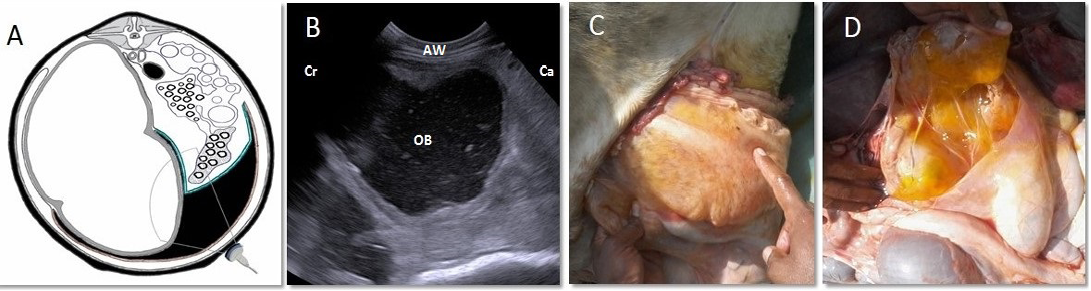

Omental bursitis of 4-years-old-cow. A. Cross-section schematic diagram of abdomen at the level of 4th lumbar vertebra. Note the site of inflamed bursa and the location of transducer. B. Ultrasonogram of the same location showing an extensive collection of anechoic exudate with echogenic debris filling the space between superficial and deep layers of greater omentum. C, D. Lesions noticed at necropsy. Note presence of enlarged sac “omental bursa” containing yellowish, gelatinous exudate. AW: abdominal wall; Cr: cranial; Ca: caudal; OB: omental bursa